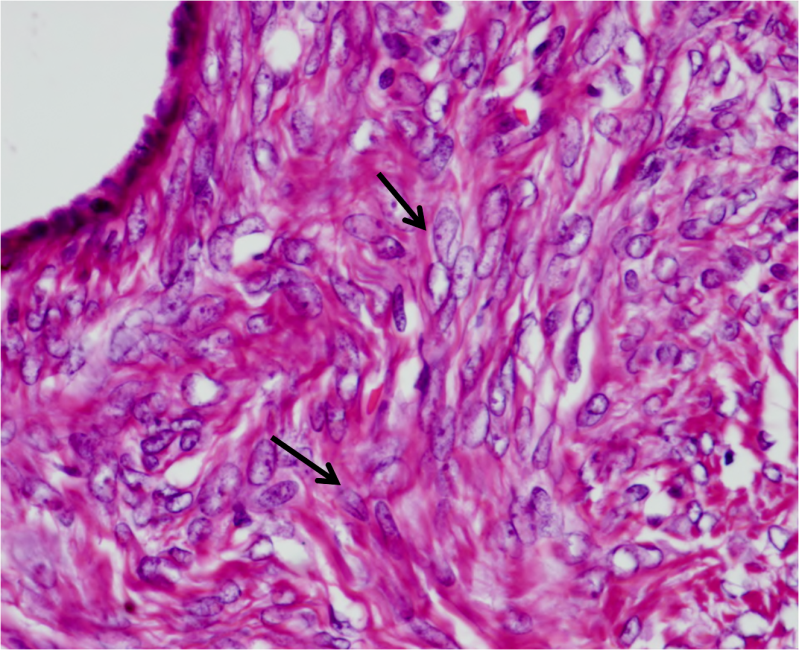

Microscopic sections from left ovary revealed variable sized cysts lined by single layered tall columnar mucin secreting epithelium of endocervical type. The epithelial cells stained positive with mucicarmine. Goblet cells were not identified. The epithelium did not divulge any evidence of atypia, increased mitosis or multilayering. Intimately admixed with the benign mucinous component were diffuse sheets of plump to ovoid cells with uniform round to oval pale nuclei, many with longitudinal nuclear grooves and indistinct cytoplasm reminiscent of granulosa cells. (Figure 1) Focal thecomatous areas and Call Exner bodies were seen.

Figure 1 Granulosa cells with ovoid nuclei and occasional nuclear grooves (arrows). Columnar mucinous epithelium in left upper corner.